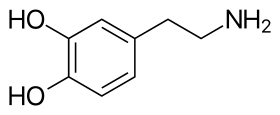

Skeletal formula of dopamine | |

Structure

A dopamine molecule consists of a catechol structure (a benzene ring with two hydroxyl side groups) with one amine group attached via an ethyl chain.[15] As such, dopamine is the simplest possible catecholamine, a family that also includes the neurotransmitters norepinephrine and epinephrine.[16] The presence of a benzene ring with this amine attachment makes it a substituted phenethylamine, a family that includes numerous psychoactive drugs.[17]